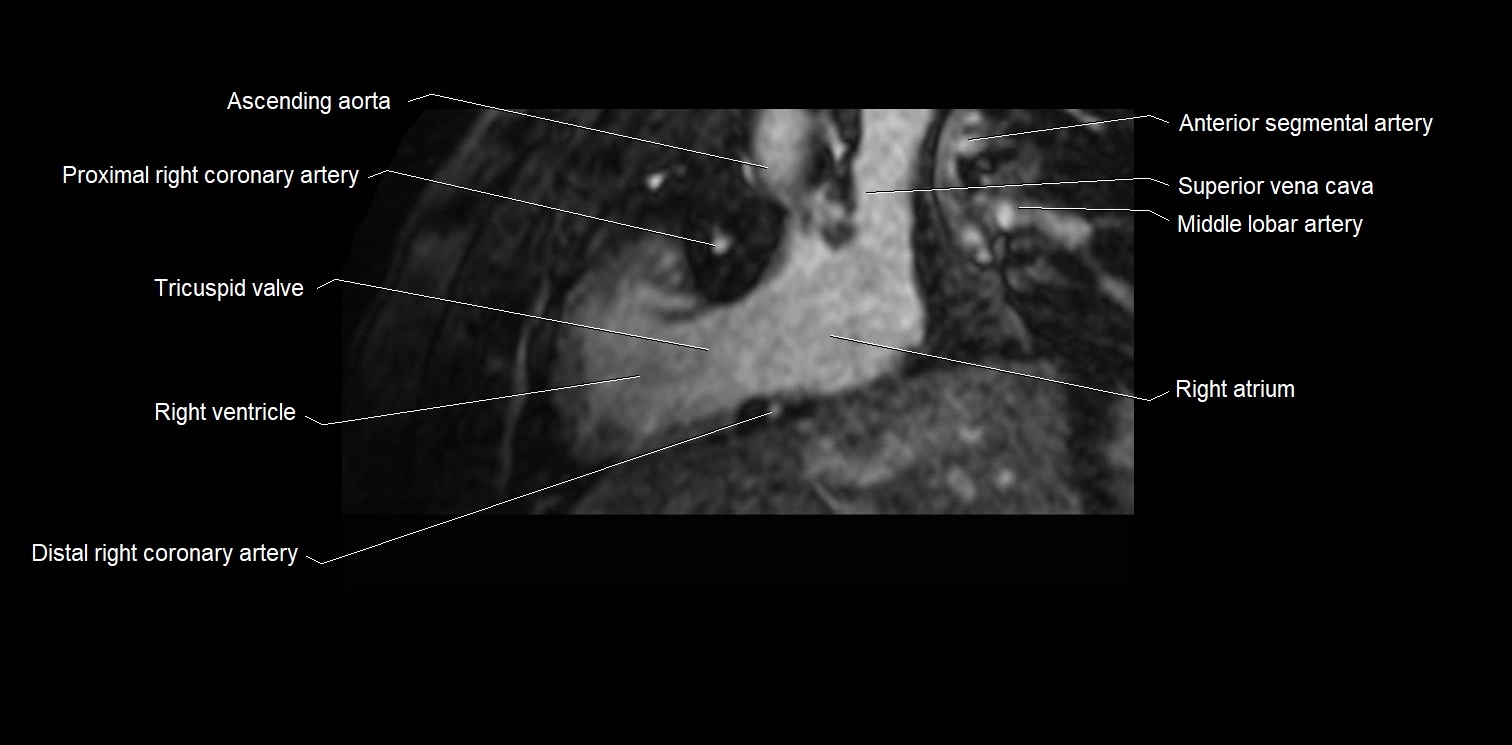

MRI image